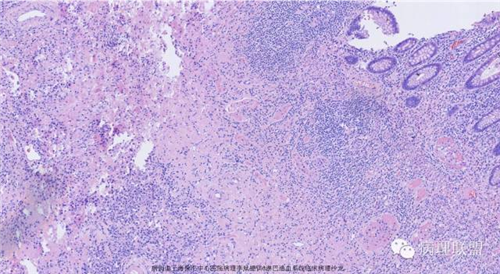

M,79岁,右半结肠粘膜下肿块。大小:6.5*6*6cm球形肿块,切面灰白质硬,界清。第一次取材。